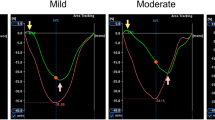

The regional mean RV midwall strain-time curves for the 5 volunteers are plotted in Figures 5 and 6. Figure 5 shows the mean of the principal strains E2 and E3, while the 1D tangential circumferential and longitudinal strains are shown in Figure 6. The data are represented as mean ± one standard deviation. A summary of the maximum strain and the time to peak strain for each RV anatomical region is given in Table 1.

The inflow region has the lowest peak strain value of all the regions, while the outflow region generally reaches the highest peak strain. However, Figure 6 illustrates that during tangential shortening in the circumferential direction, the apical region tends to have a slightly greater strain than the outflow region. Good consistency between the patterns of strain evolution is shown for the various strain estimates in Figures 5 and 6. The four regions each arrive at a maximum strain at slightly different time points in the cardiac cycle. The time sequence of regional myocardial shortening, as confirmed by all strain estimates is: inflow, outflow, mid then apical.

Both the peak strain and the time to peak strain were found to vary across the different RV regions. The inflow region consistently demonstrated lower strains and early strain peak times, while the apex consistently showed larger strain values and later peak times. Some variation does exist in the outflow region when comparing the different strain calculation types.

As there is no current standard for dividing the RV, and multiple approaches for calculating strain have been adopted, it is difficult to make a direct comparison with results from previous studies. In general, however, the magnitude trends and timing parameters of the strain measurements from this study compare favorably with previous RV studies using myocardial tagging, SENC and DENSE. From our study the peak mean principal strains values in the apical, mid and outflow regions are -0.17, -0.16 and -0.18, respectively. These values are similar to the corresponding values of -0.17, -0.19 and -0.22 reported in a tagging study by Haber et al. [4].

In the SENC study by Hamdan et al. [9], they show longitudinal strains to be largest at the base, with a lower strain at the apex, and the lowest strain in the mid region. For circumferential strain they show the largest strain at the apex, with a lower strain in the mid and basal regions. These regional strain comparisons show excellent agreement with those presented in Table 1. In our results, during longitudinal contraction, the largest strain is found in the outflow region (basal), followed by the apical and mid regions, while circumferential strain in the apical region is larger, followed by the mid and outflow (basal) regions.

The 1D peak longitudinal strains in Table 1 are all larger than the corresponding 1D peak circumferential and mean principal strains, a result confirmed in tagging studies by both Haber et al [4] and Fayad et al. [19]. Fayad et al., who used a very similar method to ours for sub-dividing the RV, found regional peak circumferential strains to range from largest to smallest in the following order: apical, mid, inflow and outflow. For peak longitudinal strains the corresponding order was: outflow, inflow, apical and mid regions. The peak strain values in Table 1 also correlate well with the segmental shortening presented by Fayad et al., except for the inflow region where our values are consistently lower.